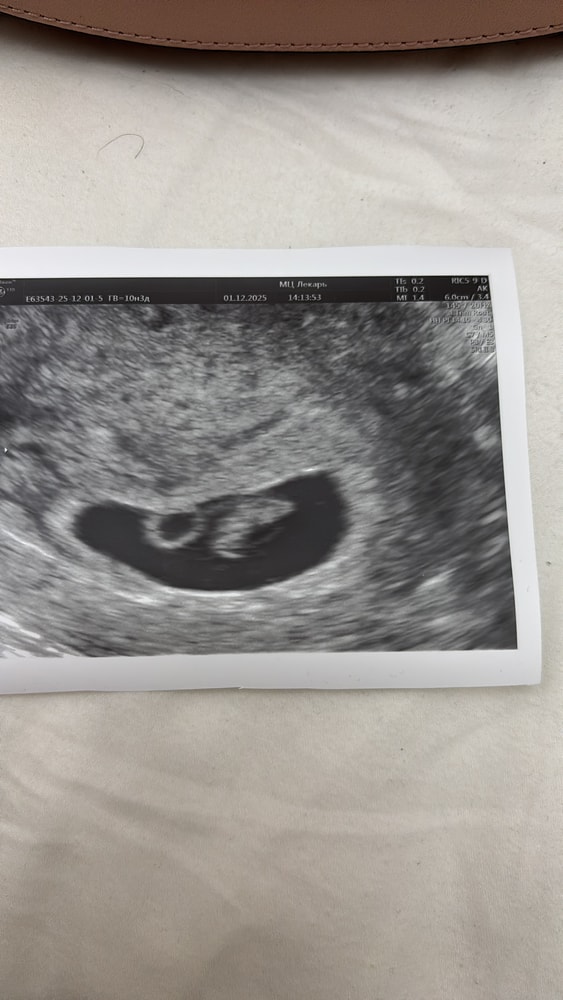

Хочу прикрепить фото и результаты первого узи и 2 которую проверили сего . У меня была истерика потому что в первый раз сказали что двойня но я надеюсь на лучшее и жду чудо. На 2 узи сказали что один плод , щас я не знаю как с этим смирится , и как понять один плод или 2. Но я до сих пор надеюсь что у меня там будут двоя